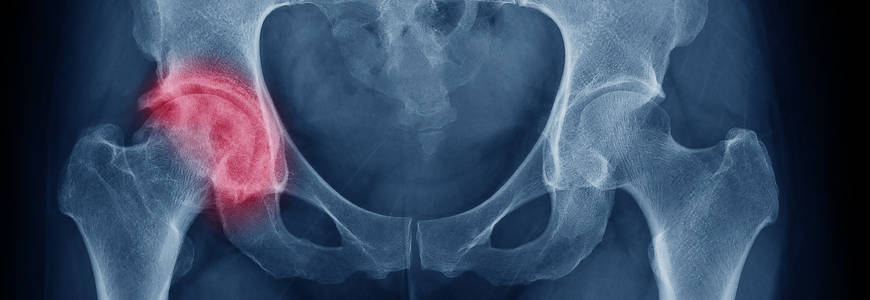

髋关节镜手术 关节镜微创手术主要针对髋关节撞击综合症 , 表现为股骨头颈和髋臼之间异常的凸起 , 屈髋时会发生碰撞 , 弯腰 , 下蹲 , 爬楼梯会产生疼痛 , 髋关节活动角度受限 , 疼痛部位多发生于臀部 , 腹股沟 , 有时候辐射到膝盖和背部 。